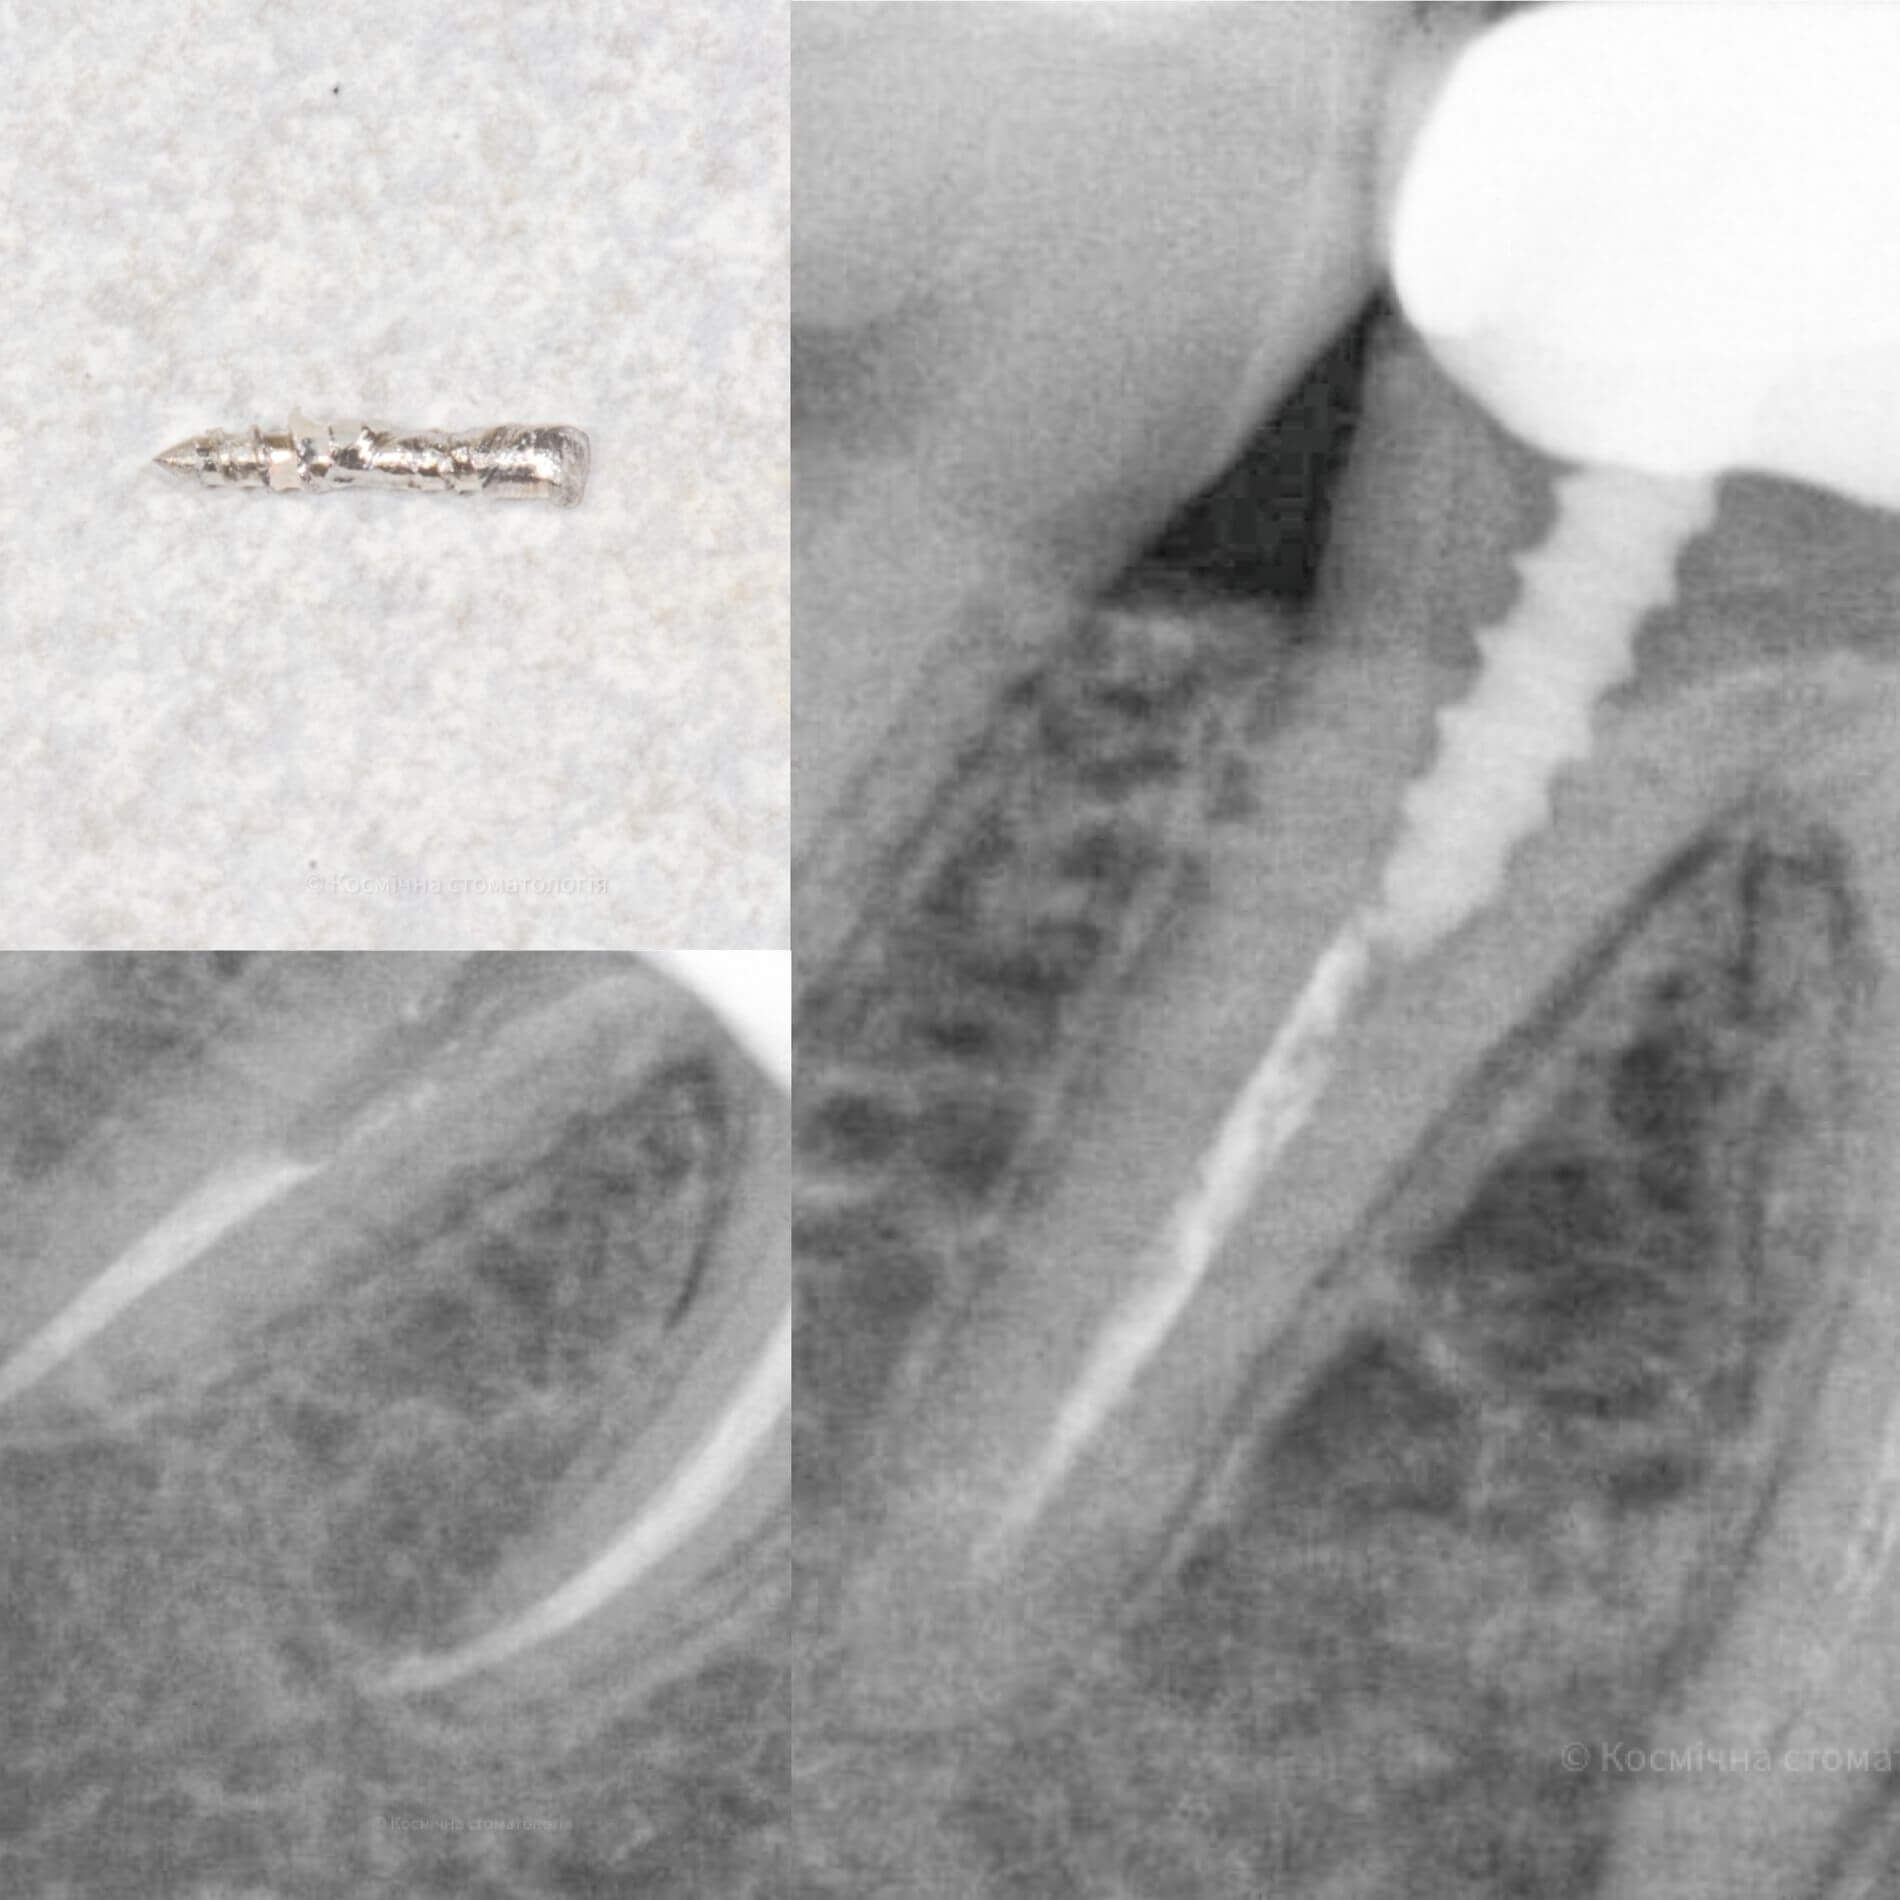

Мы уже говорили, качественное лечение зубных каналов – это довольно сложный и трудоемкий процесс, но с ним с легкостью справится наша космическая команда. Эта процедура затруднена отсутствием полноценного доступа к операционной полости, да еще зубные каналы часто искривлены и очень узкие, что делает невозможным визуальный контроль за проведением процедуры.

Но инновационные технологии и применение рентгенологического контроля выводят лечение каналов зуба во Львове специалистами Космической стоматологии Драганчука на новый межгалактический уровень.

Чтобы провести процедуру лечения и пломбирования каналов, мы в космической стоматологии Драганчука используем оптическое увеличение с помощью микроскопа Carl Zeisse.

Он позволяет вывести изображение на большой экран и масштабировать его, чтобы наша космическая команда могла осуществить все необходимые манипуляции особенно скрупулезно. Благодаря такому оптическому контролю каждого этапа лечения, мы можем оценить его эффективность и предотвратить возникновение осложнений.